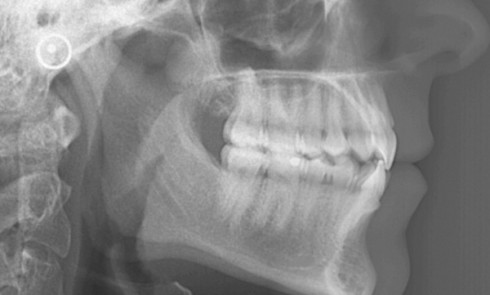

Article réservé à nos abonnés Classe II ortho-chirurgicale ou « l’appétit vient en mangeant »

Madame P., âgée de 43 ans, consulte pour la première fois en octobre 2012 et nous dit : « J’ai l’impression que mes...